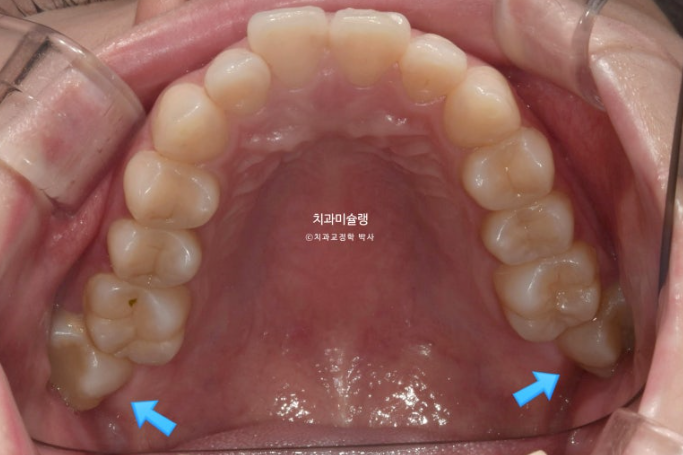

파란 화살표 부분은 위 아래 큰어금니가 엇갈려 물리는 가위교합입니다.

파란화살표 두번째 큰어금니가 바깥으로 밀려나가 가위교합이 된 것 입니다.

가위교합의 개선을 위해서는 입천장에 교정용 나사가 필요합니다.

앞니를 최대한 뒤로 많이 넣어야 하는 상황이라서 입천장뿐 아니라 볼쪽에도 교정용 나사를 심고 진행했습니다.

파란 화살표 큰어금니가 입천장쪽으로 들어오면서 가위교합이 해소가 되었습니다.